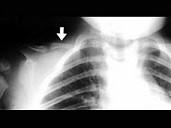

男,2岁,发育迟缓,头颅软,结合图像,最可能的诊断是?(?)A.成骨不全B.颅锁骨发育不全C.马方综合征D.软骨发育不全E.黏多糖病

问题 男,2岁,发育迟缓,头颅软,结合图像,最可能的诊断是?(?)

选项 A.成骨不全 B.颅锁骨发育不全 C.马方综合征 D.软骨发育不全 E.黏多糖病

答案 B